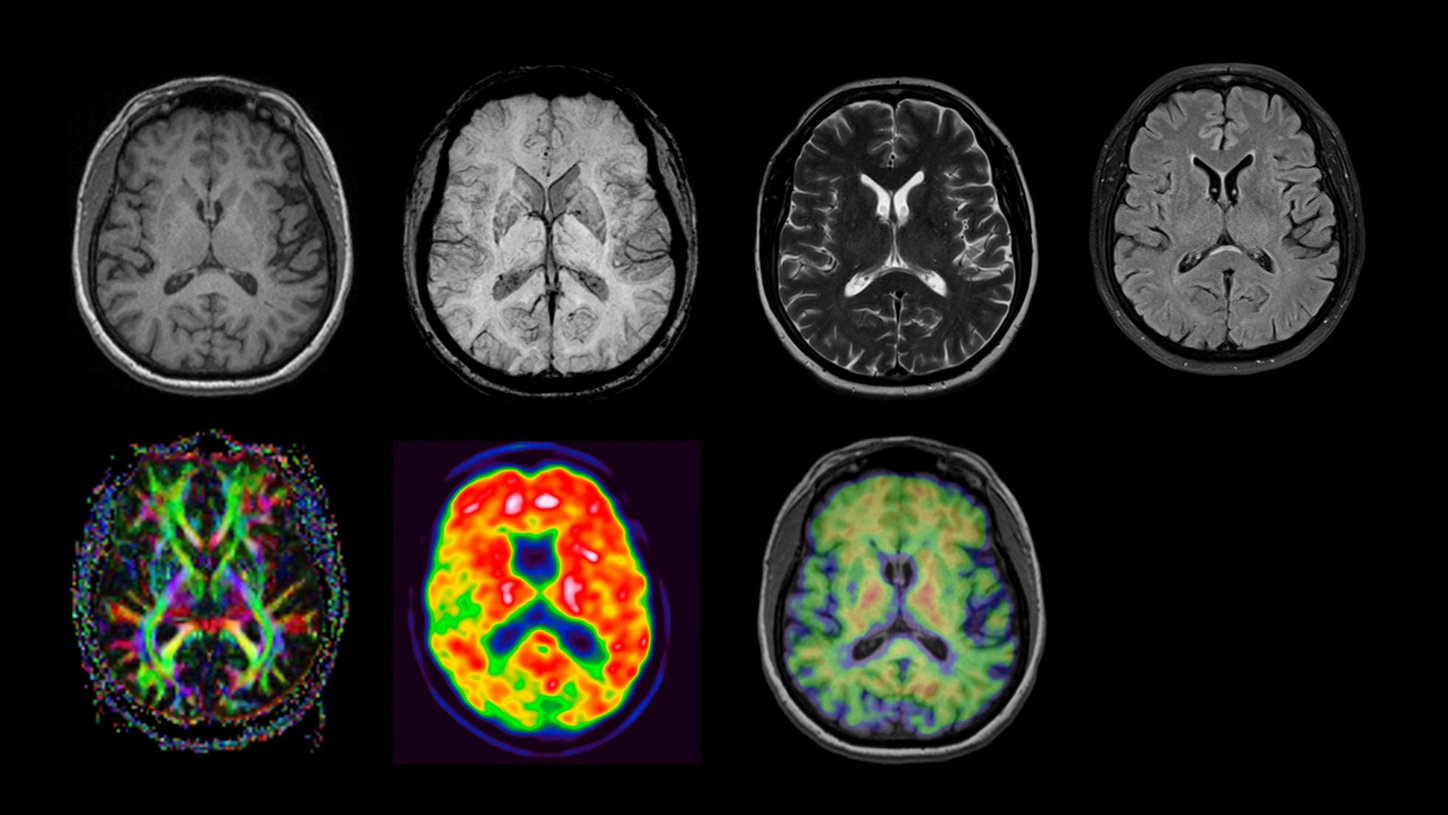

BIOGRAPH One is designed to excel in PET/MR precision to support confident diagnostic decisions. Featuring the Optiso UDR Pro detector with the largest 35 cm axial FOV2 in PET/MR, it is designed to enable comprehensive capture with excellent sensitivity and ultra-fast TOF3 in real time – delivering clear, detailed images.

Planned with Deep Resolve for accelerated acquisition and improved resolution in 2D and 3D applications4, BIOGRAPH One has the potential to make PET/MR exams faster than ever before. Designed with a powerful 3T magnet at its heart, BIOGRAPH One will deliver unparalleled performance with outstanding homogeneity, a large 55 x 55 x 50 cm³ field of view and robust gradient power.